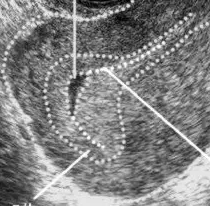

真孕囊

孕囊一般位于宫腔某一侧蜕膜内,轮廓光滑完整,张力好,与孕周基本相符;囊壁厚度一般>2mm,呈均匀一致的较强回声;可呈现双环征;孕囊内可见卵黄囊及胚胎回声,并可见原始心管搏动,卵黄囊是诊断孕囊的金标准;真孕囊可随孕龄生长。